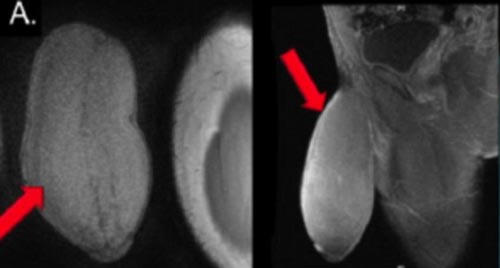

Các bác sĩ phẫu thuật cho chàng trai thực sự bị sốc khi cậu tìm đến chỗ họ than phiền về "súng ống quá khủng". Khi ở trạng thái ỉu xìu, nó có số đo chiều dài gần 17,8cm với chu vi tới 25,4cm, tức là tương đương kích cỡ một quả bưởi. Các chuyên gia phẫu thuật thậm chí mô tả "cậu nhỏ" đặc biệt này có hình dạng của một quả bóng bầu dục.

Cuối cùng, nhóm của tiến sĩ Carrion quyết định sử dụng một kỹ thuật phẫu thuật thường dùng để chữa trị bệnh Peyronie, một hội chứng trong đó mô sẹo phát triển quanh dương vật, khiến nó bị cong gập. Họ đã cắt bỏ 2 mảng mô hai bên dương vật, nhưng khéo léo vòng tránh niệu đạo (ống chứa nước tiểu xuyên qua dương vật) và tất cả các dây thần kinh đem lại cảm giác ở vùng sinh dục.